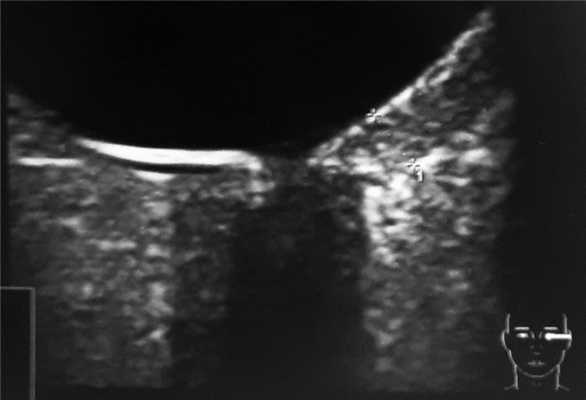

Располагаясь в центральной зоне, гемангиома почти в 2/3 случаях поражает макулярную и парамакулярную области. Юкстапапиллярное расположение гемангиомы, по нашим данным, встречается у 1/3 больных (рис. 2).

С учетом локализации опухоли ранним признаком ее, заставившей больных обратиться к офтальмологу, практически во всех случаях явилось снижение зрения. К моменту обследования гемангиома имела толщину, равную в среднем 3±0,7 мм (от 1,6 до 3,9 мм), а основание ее достигало в среднем 8,9±3,2 мм (от 3,8 до 13,5). Во всех случаях имелась вторичная отслойка сетчатки (в 6 случаях плоская, в 3-х - высокая).

При УЗ-сканировании у всех больных определялся проминирующий гиперэхогенный очаг без «экскавации» хориоидеи с ровной поверхностью.

При исследовании в режиме ЦДК во всех случаях, независимо от размеров отграниченной гемангиомы, выявлено равномерное распределение новообразованных сосудов по всей ее толщине и площади. Визуально кровоснабжение гемангиомы осуществляется за счет сосудов хориоидеи: сосуды сетчатки не участвуют в ее питании (рис. 3, 4) Только при юкстапапиллярной локализации (3 случая) опухоль получала двойное кровоснабжение - за счет сосудов хориоидеи и ЦАС (рис. 5).